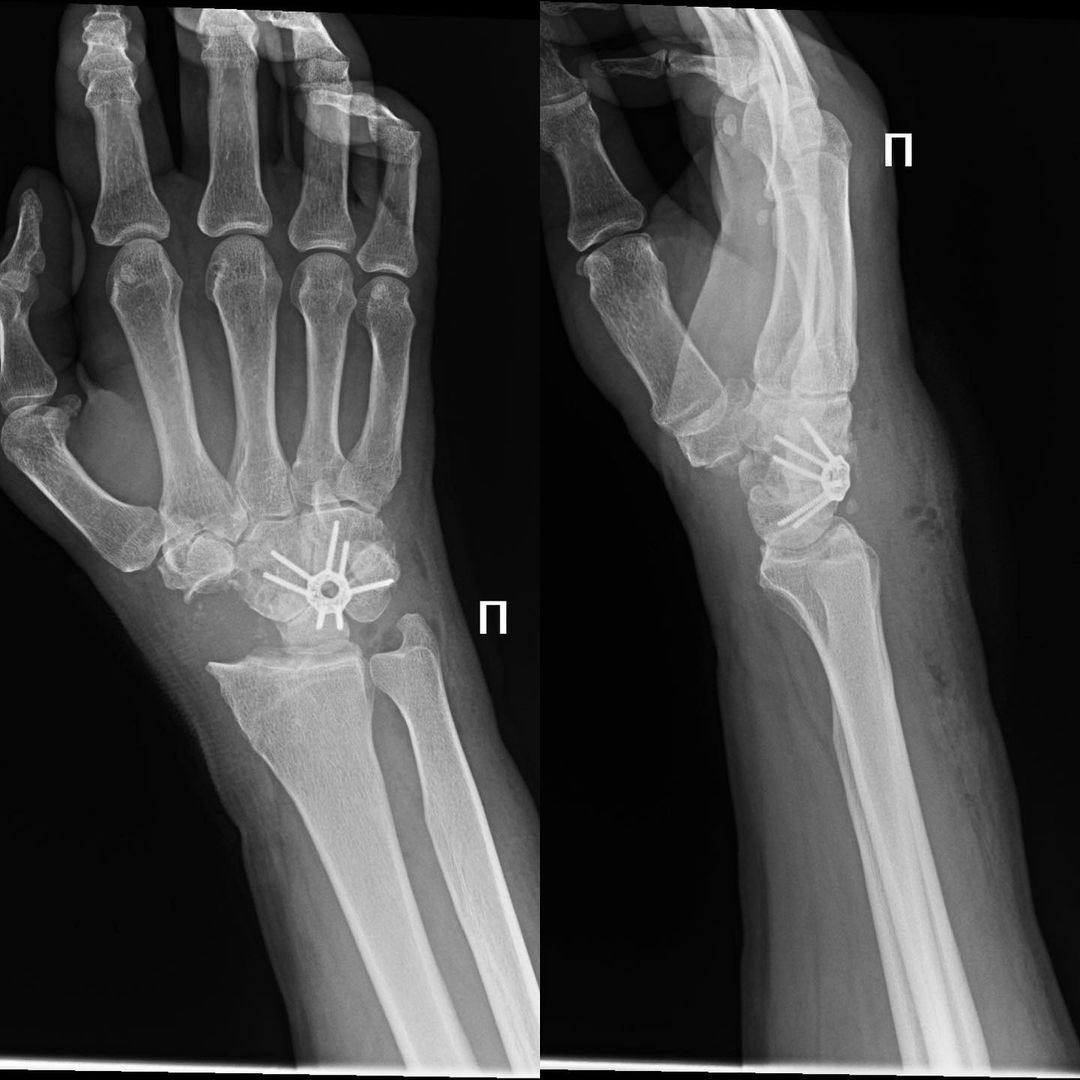

Для решения проблемы Гайк Каренович выполнил операцию – парциальный артродез.

Благодаря этому:

• Боли в руке резко уменьшились;

• Объем движений увеличился.

Пациент доволен результатом, качество его жизни значительно повысилось.

Но полностью восстановить функцию лучезапястного сустава через столько лет после травмы невозможно.